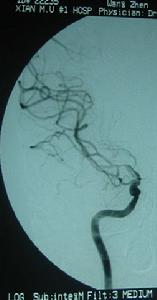

概括來說,它的基本病因主要有兩個方面:即血管病變基礎與血管內流動著的血流動力學基礎。前者以動脈粥樣硬化或(和)高血壓性細小動脈硬化、動脈炎為多見;後者主要為血液成分改變與包括血壓因素在內的血流動力學改變。當管壁粗糙、血流緩慢、血壓偏低、有利於血凝時,即致缺血性中風;如果流動著的血液內含有栓子(這種栓子可來自心臟、動脈粥樣硬化上的小斑塊,甚至瘤細胞團),它們可以像塞子一樣,在流動過程中把相應管徑的血管堵塞,造成缺血性中風。